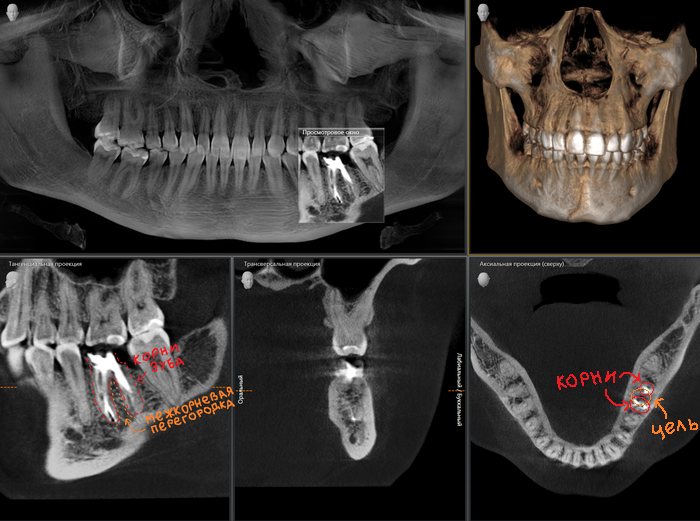

Далее выбираем следующий уровень сложности, когда приходится удалять 6-ой зуб на нижней челюсти. Зуб этот двухкорневой. Мы, конечно, не будем устанавливать по имплантату в область каждого корня, как кто-то мог подумать. Хотя я видел подобные случаи. У доктора, видимо, горел кредит по ипотеке.

Итак, нам надо установить один имплантат, но четко по центру. Целиться мы будем в костную перегородку между двумя корнями.

Устанавливаем имплантат. Слева и справа от него на снимке четко видны лунки от только что удаленного зуба, которые, по мере заживления, затянутся.

Помните, я говорил, что имплантат должен стоять по центру? Так вот 3-х корневой зуб не исключение. Имплантат устанавливается, как и в предыдущем случае, в перегородку, но уже трехкорневого зуба. Как мы видим высота кости в этой области около 3мм. Данного объема недостаточно для постановки имплантата оптимальной длины, следовательно объем нужно увеличивать. Манипуляцию проводят при помощи специального «костного материала». Кто-то называет его «костный порошок», не путать с «белым порошком», хотя он и белый, но представлен все-таки в виде гранул. Выпускается как просто в стеклянной таре,

Как мы видим условия в данном случае несколько хуже около 2мм. Но это не помешало нам провести операцию в полном объеме.